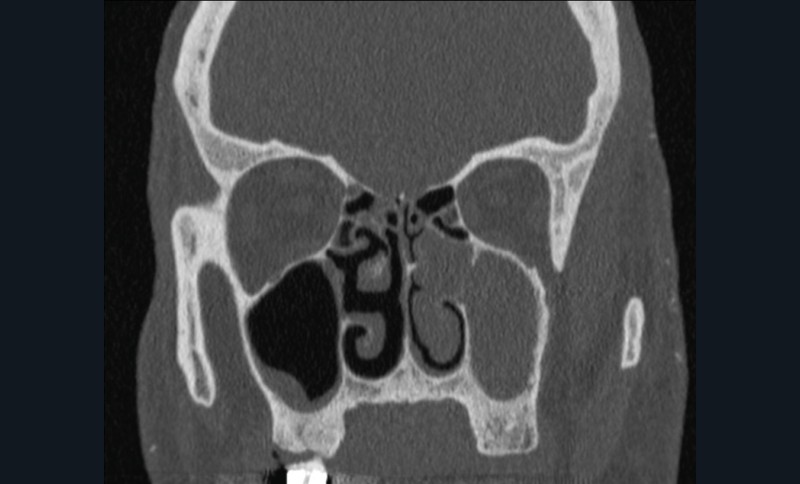

La tomodensitométrie des sinus retrouve un comblement complet unilatéral du sinus maxillaire gauche et des cellules ethmoïdales antérieures homolatérales, sans image de densité calcique intrasinusienne et sans lyse osseuse des parois (fig. 1). L’IRM montre un épaississement tissulaire de 23 mm de grand axe en regard du méat moyen gauche, avec un aspect de signal T2 hétérogène (fig. 2) et prenant le contraste en masse (fig. 3). Le comblement maxillaire gauche associé à un épaississement muqueux en cadre rehaussé correspond à une rétention en hypersignal en diffusion (fig. 4), avec diminution du coefficient apparent de diffusion (moyenne à 433 mm2/s) en faveur d’une pyocèle (fig. 5).